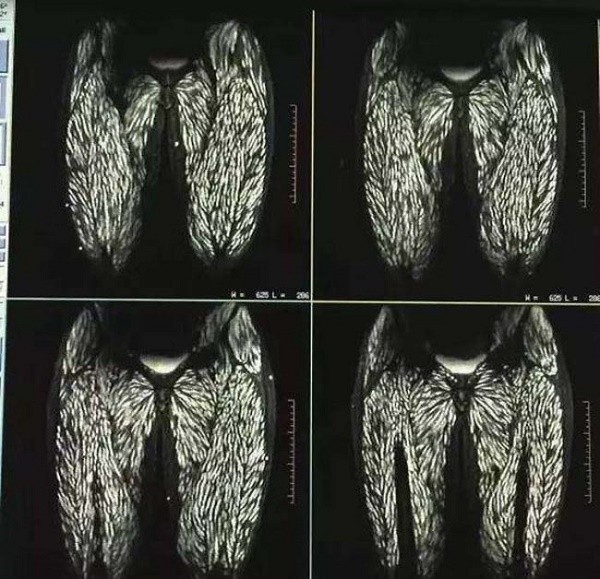

Sán dày đặc trên 2 lá phổi của người phụ nữ.